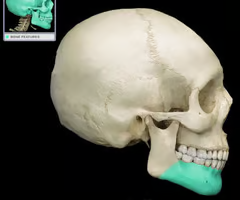

Hyoid bone (only bone that does not articulate directly with any other bone)

Mandibular angle (where ramus and body meet)

Body (forms the chin)

Mandibular foramen (nerves involved in tooth sensation - pass to lower jaw teeth - dentists inject Novocain to numb lower teeth)